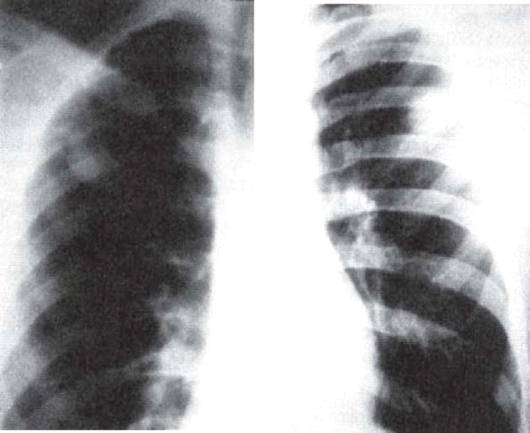

Округлый инфильтрат представлен ограниченным

(фокусным) затемнением округлой формы, преимущественно средней интенсивности с

ясными, но не резкими очертаниями(рис. 11.6).

а б

Рис. 11.6. Округлый инфильтрат во II сегменте

правого легкого (а) и во II сегменте левого легкого (б). Фрагменты

рентгенограмм легких в прямой проекции.

Рис. 11.7. Инфильтрат Ассманна-Редекера в левом

легком. Фрагменты рентгенограмм легких в прямой проекции.

На обзорной рентгенограмме в прямой проекции затемнение часто локализуется в подключичной области (классический тип инфильтрата Ассманна-Редекера, рис. 11.7). От медиальных отделов затемнения к корню легкого отходит воспалительная дорожка, в которой иногда выявляют проекцию дренирующего бронха (симптом «теннисной ракетки» - рис. 11.8, 11.9). При распаде инфильтрата в его центральных отделах обычно выявляются образовавшиеся полости (рис. 11.10). В нижележащих отделах легкого нередко заметны очаги бронхогенного обсеменения. При томографии в инфильтрате иногда можно обнаружить плотные и кальцинированные очаги - важный признак туберкулезной этиологии поражения.